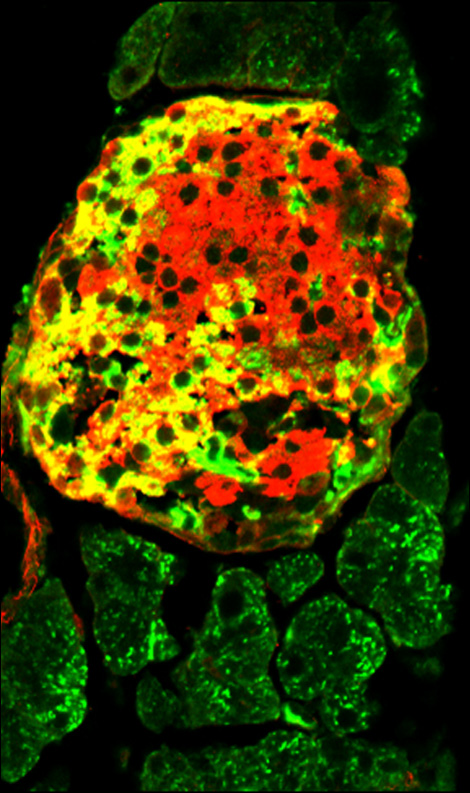

稲田特任准教授によると、β細胞は体重の増加につれて増える。それも生後の発育期には急激な増え方をする。β細胞の根源は膵管上皮細胞にあると考え、数年かかって膵管上皮細胞に特異的に発現する遺伝子を特定することにまず成功した。この遺伝子に印をつけてマウスの成長に伴う変化を観察することを思いつき、膵管上皮由来細胞は緑、インスリンを分泌する細胞は赤と、それぞれ色分けしてみたところ、生後4週間までにはインスリンを分泌する細胞集団(赤)の中に、膵管上皮由来の細胞(緑)が存在していた。

次に別のマウスを使って、膵臓を損傷したマウスが組織を再生する過程を調べると、やはり膵管上皮細胞からβ細胞へと分化していく状況を、同じ色分け方法で確認することができた。稲田特任准教授によると「β細胞の幹細胞(前駆細胞)は膵管上皮に存在すると長い間言われているが、直接実証できたのはこれが初めてだ」という。

〈写真説明〉膵臓を損傷したマウスの再生過程で、膵管上皮からβ細胞に分化した細胞が黄色で示されている。